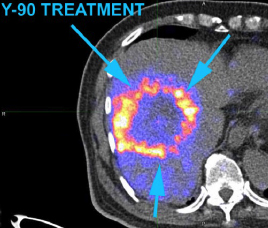

- 用正電子/電腦雙融掃描顯示釔90粒子分佈(右)

99mTc MAA SPECT/CT Y-90 PET/CT

- 治療後3個月正電子/電腦雙融掃描

- 肝臟腫瘤代謝活躍度和體積減少

- 甲胎蛋白水平減少至1206 ng/ml

C-11 Acetate F-18FDG